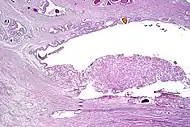

Intraductal carcinoma

Intraductal carcinoma of the prostate gland (IDCP), which is now categorised as a distinct entity by WHO 2016, includes two biologically distinct diseases. IDCP associated with invasive carcinoma (IDCP-inv) generally represents a growth pattern of invasive prostatic adenocarcinoma while the rarely encountered pure IDCP is a precursor of prostate cancer.[19] The diagnostic criterion of nuclear size at least 6 times normal is ambiguous as size could refer to either nuclear area or diameter. If area, then this criterion could be re-defined as nuclear diameter at least three times normal as it is difficult to visually compare area of nuclei.[19] It is also unclear whether IDCP could also include tumors with ductal morphology.[19] There is no consensus whether pure IDCP in needle biopsies should be managed with re-biopsy or radical therapy. A pragmatic approach would be to recommend radical therapy only for extensive pure IDCP that is morphologically unequivocal for high-grade prostate cancer.[19] Active surveillance is not appropriate when low-grade invasive cancer is associated with IDCP, as such patients usually have unsampled high-grade prostatic adenocarcinoma.[19] It is generally recommended that IDCP component of IDCP-inv should be included in tumor extent but not grade.[19] However, there are good arguments in favor of grading IDCP associated with invasive cancer.[19] WHO 2016 recommends that IDCP should not be graded, but it is unclear whether this applies to both pure IDCP and IDCP-inv.[19]

Intraductal carcinoma of the prostate with an infiltrative growth pattern may be morphologically difficult to distinguish from invasive cancer. One focus shows comedonecrosis (arrow), morphologically suggesting Gleason pattern 5 invasive carcinoma (a haematoxylin and eosin, b CK5/6)[19]

Intraductal carcinoma of the prostate with very patchy basal cells identified by immunohistochemistry. At least some of the glands lacking basal cell immunoreactivity represent intraductal rather than invasive carcinoma (a haematoxylin and eosin, b CK 5/6)[19]

Ductal adenocarcinoma may have a prominent cribriforming architecture, with glands appearing relatively round, and may thereby mimic intraductal adenocarcinoma, but can be distinguished by the following features:[10]

| Feature | Ductal adenocarcinoma | Intraductal adenocarcinoma |

|---|---|---|

| True fibrovascular cores in micropapillary architecture | Present | Usually absent |

| Cribriform lumens | Lined by pseudostratified, columnar cells | Punched out lumens lined by cuboidal cells |

| Basal cell markers | Usually negative | Usually positive |